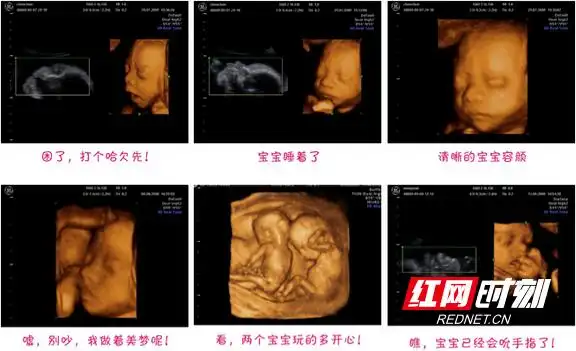

3月2日,钟嘉欣[微博]在微博上宣布自己已怀有二胎,并晒出了宝宝的b超

现已怀有8个多月身孕的霍思燕,与8月19日通过微博晒腹中胎儿b超照,并